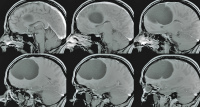

Fallbericht: Blickdiagnose "Arachnoidalzyste" erweist sich als Irrtum: akute Symptomatik einer 14 Jahre alten supratentoriellen endodermalen Zyste

Journal für Neurologie, Neurochirurgie und Psychiatrie 2015; 16 (4): 178-182 Volltext (PDF) Praxisrelevanz Abbildungen